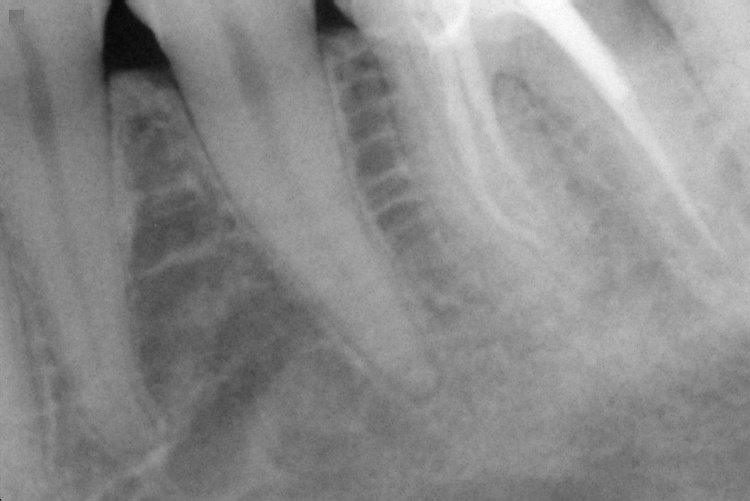

Name Last modified Size Description Parent Directory - IO000001.jpg 2020-07-28 13:55 84K IO000002.jpg 2020-07-28 13:55 68K IO000003.jpg 2020-07-28 13:55 83K IO000004.jpg 2020-07-28 13:55 92K